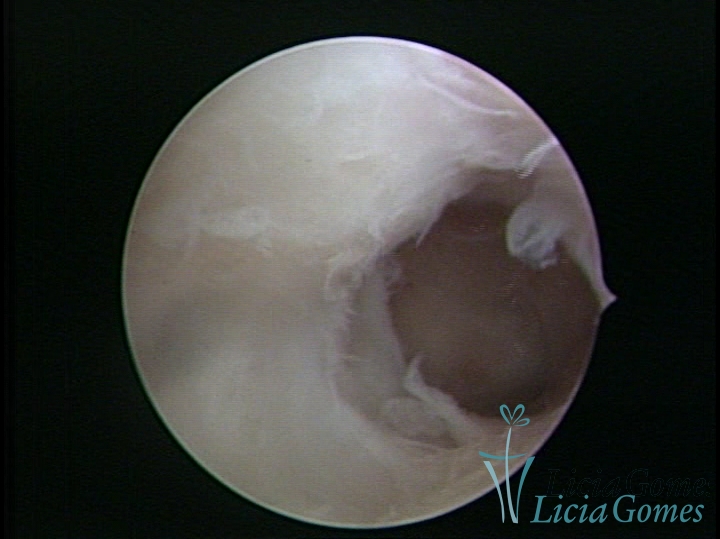

• SINÉQUIA TIPO FIBROMUSCULAR